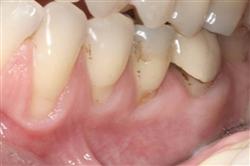

Cosmetic Soft Tissue Grafting

In addition to the functional problems previously mentioned, receding gums can look unsightly.

Longer looking teeth and exposed tooth roots give an "old" appearance to your smile. Some people cover their mouths when they smile for this very reason.